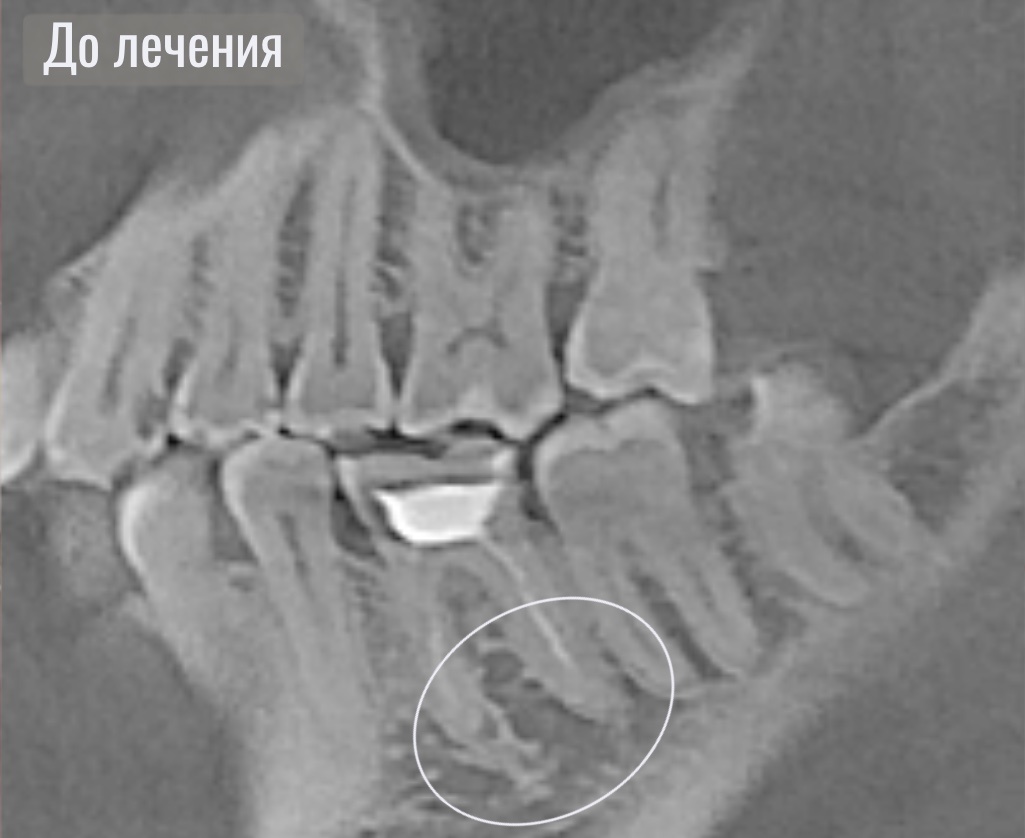

Периодонтит на снимке

По данным осмотра и рентгенодиагностики был выявлен хронический очаг инфекции зуба хронический периодонтит.